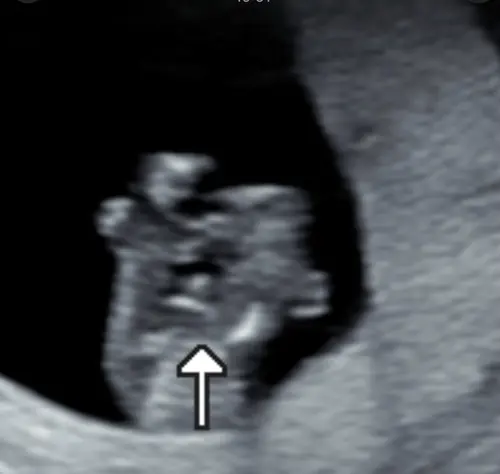

Moeders! Ik heb al een vroege Geslachtecho gedaan 13+5. Nu zie je duidelijk dat het een jongen is alleen nu zit ik net door mijn andere foto鈥檚 te kijken en zie ik dat hij de navelstreng vast heeft馃槄. dit is toch gewoon zijn piel?

Echo met navelstreng